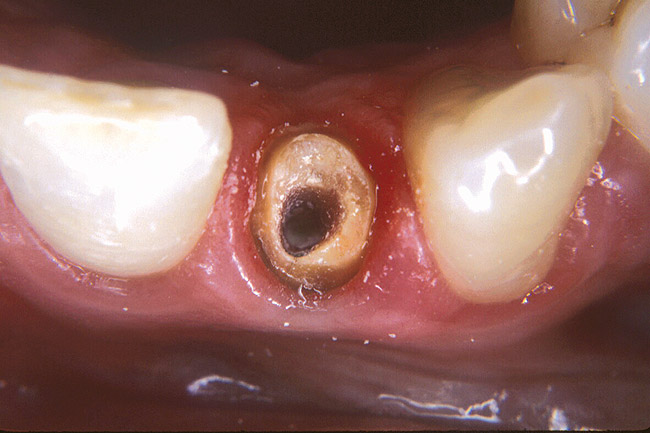

In consideration of the crown preparation, there needs to be sufficient tooth structure remaining to create a ferrule of at least 1.5 mm to 2 mm. Ferrule refers to an extension of the tooth preparation beyond the core restorative so that there is a continuous ring at least 1.5 mm to 2 mm in length of sound tooth structure 360° around the crown preparation. This ensures that the tooth has a rigidity to resist coronal leakage and fracture.58,59 This stiffness of the ferrule will ensure clinical success.60-62 An evaluation of the remaining dentin thickness at the cementoenamel junction (CEJ) is important to determine if there is sufficient tooth structure to support a crown. In the case of a thin-walled root canal, it may be necessary to plan a porcelain-metal crown to conserve the remaining tooth structure when compared to an all-ceramic crown that requires a minimum 1-mm shoulder preparation at the CEJ. If an adequate ferrule is not developed in the crown preparation, the tooth and core are at risk of fracture (Figure 6A through Figure 6C).

Figure 6a  Inadequate ferrule on maxillary central incisor crown led to fracture.

Figure 6a

Figure 6b  Central incisor after crown fracture. This was not an endodontically treated tooth.

Figure 6b

Figure 6c  Mandibular molar fracture with inadequate ferrule in crown preparation.

Figure 6c